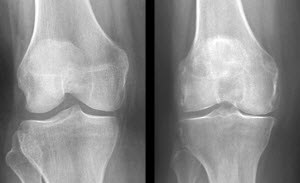

La osteoartritis se produce cuando la amortiguación natural entre articulaciones en el cuerpo se desgasta, lo que permite que los huesos se rocen. Con un estimado de 27 millones de personas de sucumbir a la osteoartritis, hay un interés significativo en la búsqueda de formas para prevenir o tratar la condición.

Los participantes del estudio tenían entre 45 y 79 años y tuvieron al menos una rodilla con la evidencia de osteoartritis. Los investigadores se centraron en un total de 418 voluntarios para los que las concentraciones séricas de la sangre de la vitamina D y la PTH estaban disponibles y para quién las radiografías para evaluar la progresión de la artrosis de rodilla estaban disponibles. Se siguieron a los voluntarios durante 4 años, y allí la progresión de osteoartritis de rodilla fue localizada y relacionada con la vitamina D y los niveles de PTH en la sangre.

En comparación con los voluntarios con niveles saludables, los participantes con niveles bajos de vitamina D tenían más del doble el riesgo de contraer la enfermedad. Las personas que tenían tanto altas concentraciones de PTH, vitamina D baja tenían tres veces más probabilidades de empeorar durante el estudio que aquellos con niveles normales de ambos.